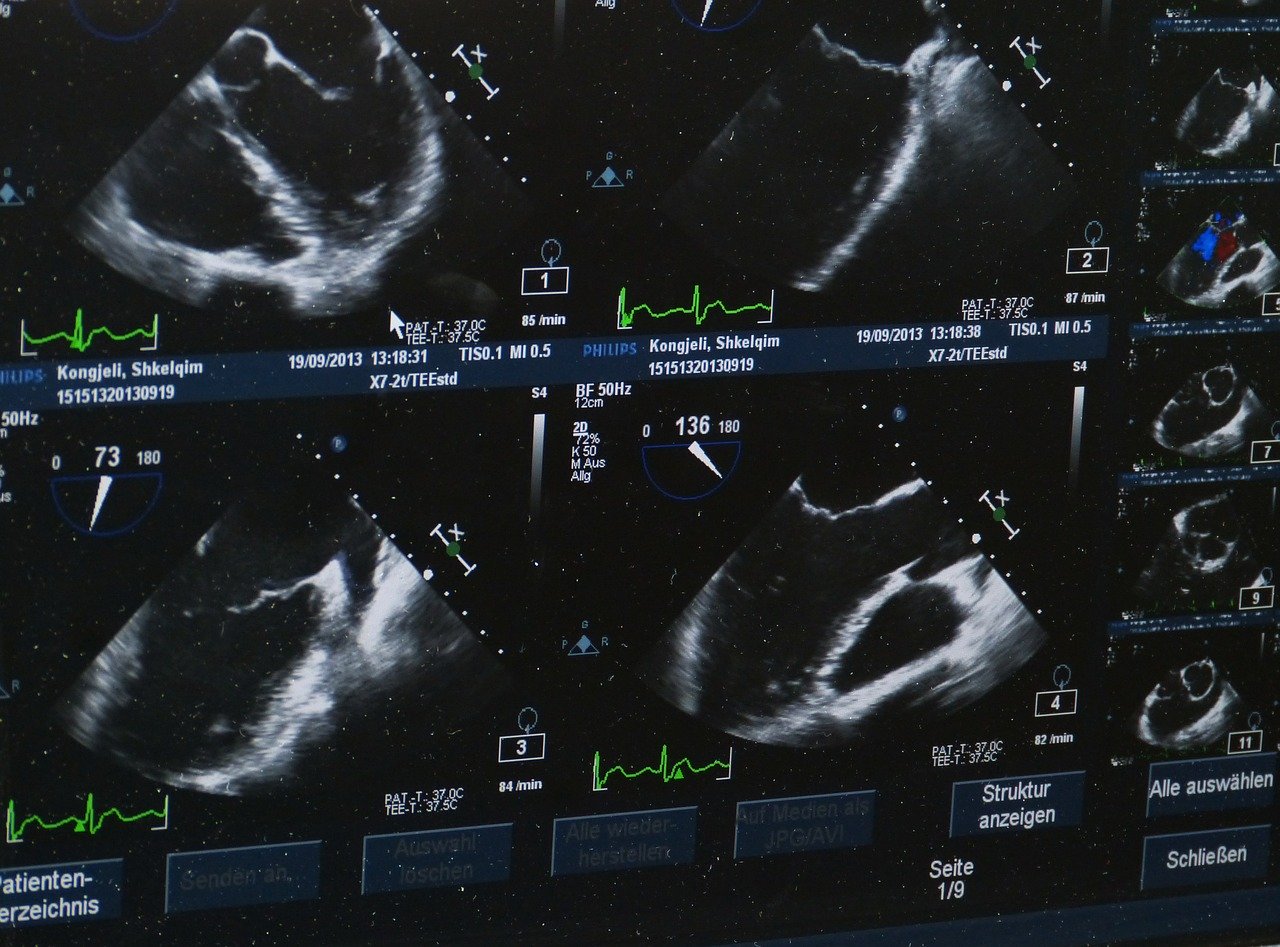

The impulses are partially reflected from certain organs, absorbed, and spread further. After returning the reflected signals, the processor calculates the distance between the organs, processes the information received and converts it into a picture on the oscilloscope screen.

The best modern ultrasound machines can have several visual modes to improve image quality: